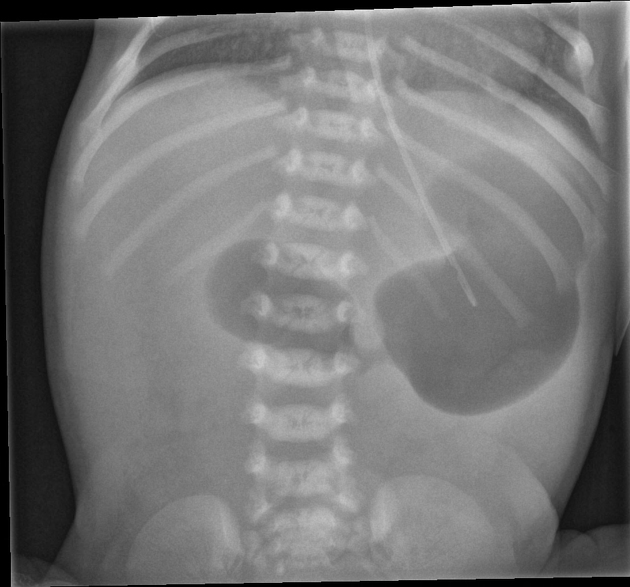

What is the diagnosis based on the image shown

Explanation: ***Bladder exstrophy*** - The image distinctly shows an **exposed urinary bladder** on the abdominal wall, a hallmark of bladder exstrophy. - This congenital anomaly results from a **failure of midline closure** of the infraumbilical abdominal wall and bladder. *Omphalocele* - An omphalocele involves protrusion of **abdominal viscera** (intestines, liver) into the base of the umbilical cord. - The herniated organs are typically **covered by a sac** composed of peritoneum and amnion, which is absent in the image. *Umbilical hernia* - An umbilical hernia is a protrusion of abdominal contents through the **umbilical ring**, but the skin remains intact and covers the defect. - The image clearly shows an **exposed organ** without skin coverage, ruling out an umbilical hernia. *Gastroschisis* - Gastroschisis involves the **evisceration of intestines** through a full-thickness abdominal wall defect, usually to the right of the umbilical cord. - Unlike the image, the defect in gastroschisis is typically **much smaller** and primarily involves the bowel, not the bladder, and there is no covering sac. *Epispadias* - Epispadias is a **urethral defect** where the urethral opening is on the dorsal (upper) surface of the penis or anterior bladder neck. - While epispadias is part of the **exstrophy-epispadias complex** and often associated with bladder exstrophy, it does not present with an **exposed bladder** on the abdominal wall as seen in the image.